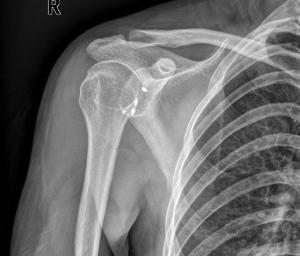

先天性肩关节脱位极其少见,文献上仅有少数个案报告。只有出生时发现肩关节脱位,才属于先天性的,即在子宫内就已形成病关节脱位。临床上所见到的常常为麻痹性的,多由于肩部肌肉麻痹所致,如分娩性臂丛神经损伤。新生儿期肩关节外伤性脱位几乎不发生。